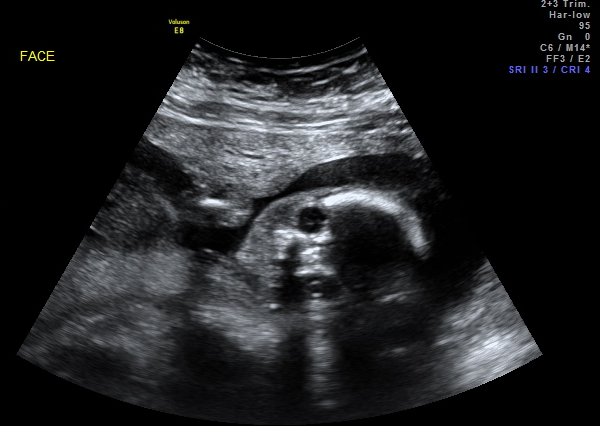

I was finally able to download the images on the CD to my computer. Well, well, well... look what we have here! Another button nose in the house!

Love that you got such a perfect head-on shot! Our little guy did that a few times, but then looked away before she could grab the photo.